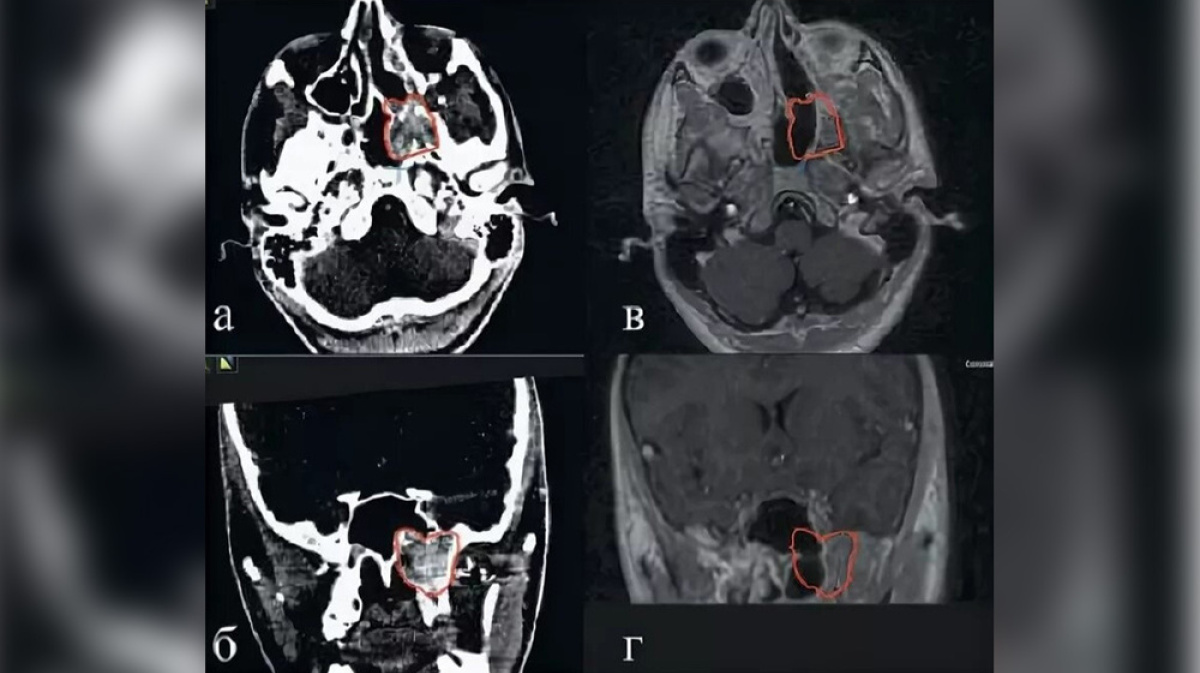

азование В Носу Фото